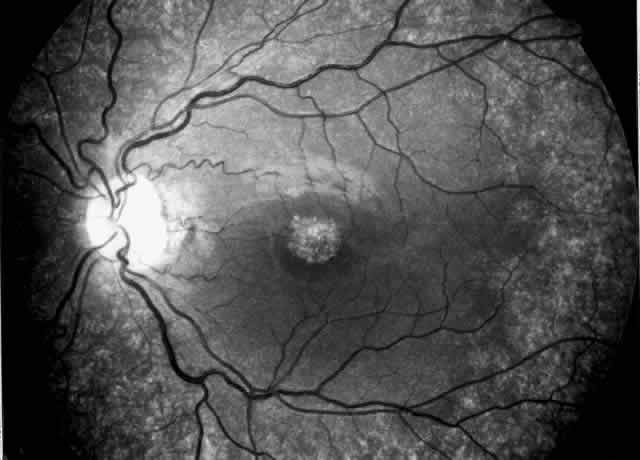

hearing loss or ocular lesions56,57 and the variants with associated leiomyomatosis or macrothrombocytopenia. Alport's syndrome may affect the cornea, lens, and retina, the most

characteristic ocular signs being posterior polymorphous dystrophy, anterior

lenticonus, and superficial perimacular flecks (Fig. 4). There is growing evidence that the ocular abnormalities, like the glomerular

lesions, result from a common defect in basement membrane formation.56,58,59 Changes are uncommon and subtle in young patients with Alport's syndrome

and seem to increase in frequency and severity with age.60 The corneal changes associated with Alport's syndrome include endothelial

opacities,58 corneal arcus, and recurrent corneal epithelial erosions.  Fig. 4. Superficial perimacular flecks in a 15-year-old boy with normal vision. Alport's

nephritis was diagnosed at the age of 3 years and progressed

to end-stage renal disease at the age of 14 years. Perceptive high-tone

hearing loss was detected at the age of 11 years. The proband's

mother has had persistent microscopic hematuria since the age of 20 years

but had no other manifestations of the disease. Fig. 4. Superficial perimacular flecks in a 15-year-old boy with normal vision. Alport's

nephritis was diagnosed at the age of 3 years and progressed

to end-stage renal disease at the age of 14 years. Perceptive high-tone

hearing loss was detected at the age of 11 years. The proband's

mother has had persistent microscopic hematuria since the age of 20 years

but had no other manifestations of the disease.